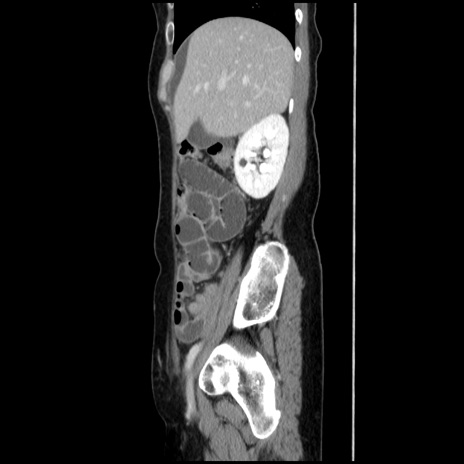

症例32(矢状断像)

冠状断像